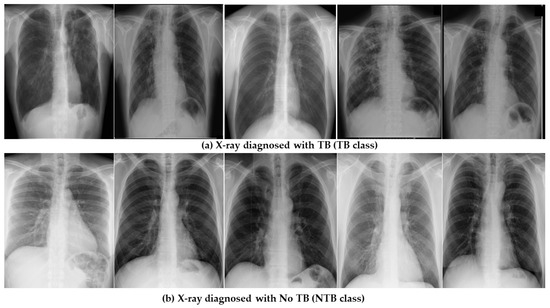

2. Data Set Description